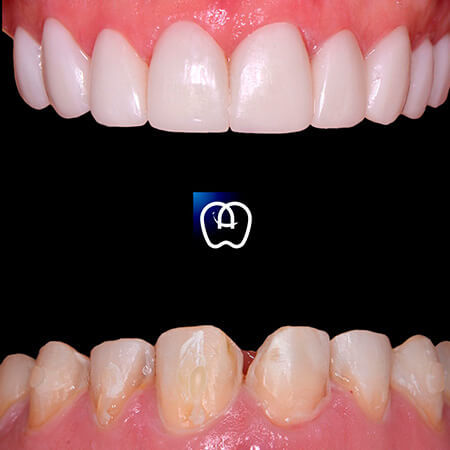

Galería de antes y después

Las especialidades de Álvarez & Arráez Odontología son: Odontólogo, Implantes dentales, Odontología láser, Odontología estética, Rehabilitación oral, Periodoncia, Endodoncia, Odontopediatra, Ortodoncia.